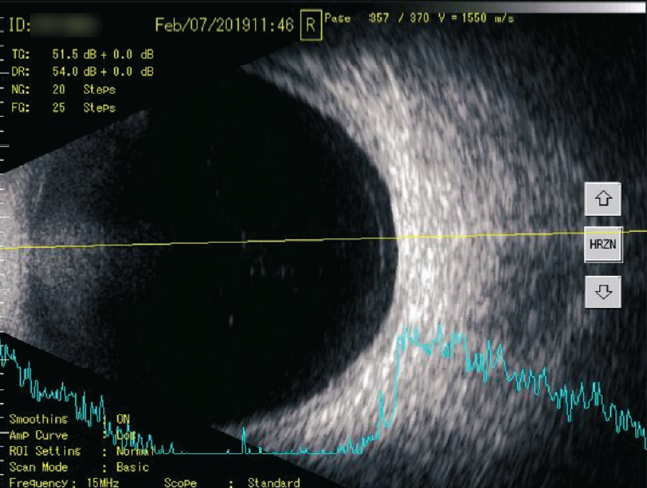

Рис. 4. A- и B-сканирование пациентки П. после курса препарата «Витрокап». В-скан: поперечная проекция по меридиану 6 ч, умеренное количество помутнений в стекловидном теле. А-скан: 12 пиков низкой эхогенности

Fig. 4. After a course of the drug “Vitrocap”, patient P.: B-scan: transverse projection along the meridian to 6 hours, moderate amount of “clouding” in the vitreous body. A-scan: 12 peaks of low echogenicity

При сканировании в В-режиме после курса лечения препаратом «Витрокап» в 32 % случаев отмечено уменьшение количества помутнений, что соответствовало снижению количества эхопиков на А-сканировании (рис. 4, 6, 8), в большинстве случаев (80 %, р < 0,05) происходило снижение высоты эхопиков при А-сканировании в зоне их максимальной концентрации (см. рис. 4, 8).